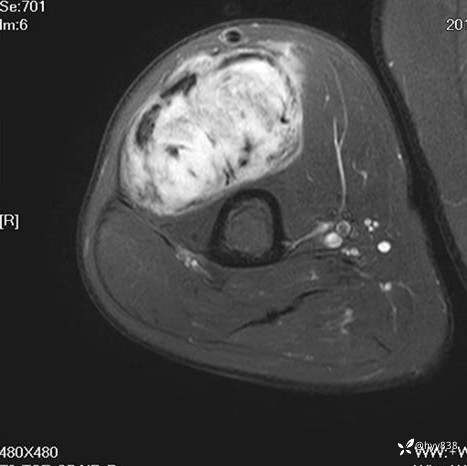

CE